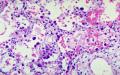

يصيب الالتهاب فصآ كامآ أو جزءآ منه أو أجزاء متفرقة من فصوص مختلفة، وتمتلتيء الحويصلات بالسوائل الالتهابية والصديد، ويمكن أن ينتقل الالتهاب إلى الدم مسببآ ما يسمى (Bacteremia) أو إلى السحايا مسببآ التهاب السحايا (Menengitis)

وبعد ذلك يأتي دور الفحص السريري، فبعد قياس درجة الحرارة والعلامات الحيوية الاخرى يفحص الطبيب صدر المريض من الامام والخلف ولابد من كشف الصدر بشكل كامل حتى يتمكن الطبيب من اجراء الفحص بشكل كاف، ويشمل الفحص النقر على الصدر من الجهتين الامامية والخلفية ثم الاستماع إلى صوت التنفس بواسطة السماعة الطبية، وبهذا يستطيع الطبيب اكتشاف وجود تغيرات أو علامات تنبيء بوجود الالتهاب

يحتاج بعض المرضى لإجراء فحوص مخبرية مثل صورة أشعة سينية للرئتين وفحص شامل للدم، بالاضافة إلى تحليل للبلغم